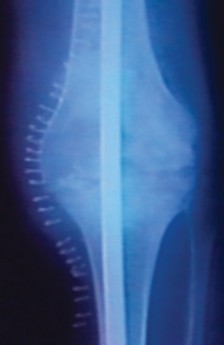

Anteroposterior and lateral plain radiographs of the affected knee and the entire lower extremity from hip to ankle are mandatory. The length of the femur and the tibia must be determined, and any unusual bowing or canal abnormalities must be identified. The length of the femur and the tibia can be obtained from plain radiographs with a measuring template in place.

Alternatively, and highly recommended, a computed tomography (CT) scan from the tip of the greater trochanter to the distal femur, and then from the proximal tibia to the distal tibia, should be utilized. CT scans are invaluable for identifying the narrowest portion of the isthmus of the tibia and femur, which dictates the maximum allowable diameter of the intramedullary nail. Coronal and sagittal CT reformats help identify endosteal sclerosis, retained cement mantles, or occult cortical defects that could lead to intraoperative fracture during reaming.

The arthrodesis nail should extend from the tip of the greater trochanter to well within the isthmus of the distal tibia. The final nail position should be within 3 to 5 inches above the tibial plafond. If there is significant distraction at the level of the knee to restore leg length, this amount of length must be meticulously calculated and added to the final nail length.